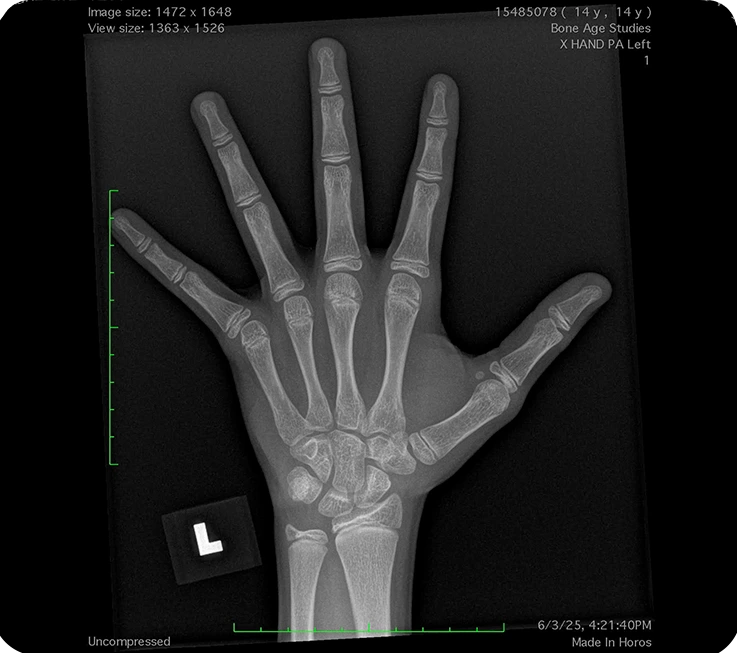

Digital X-ray file is sent to our clinic in preparation for online consultation.

After receiving your child’s X-ray results, our provider will conduct a virtual consultation to review growth potential, medical history, and treatment options. The consultation is securely conducted online via a HIPAA-compliant platform.

Follow-up blood tests are done every 6 months, and growth plate exams every 6–12 months, depending on your child’s progress. You will have a televisit with our medical providers every 3 months to ensure everything is going well. Any concerns will be promptly addressed at any time during treatment.